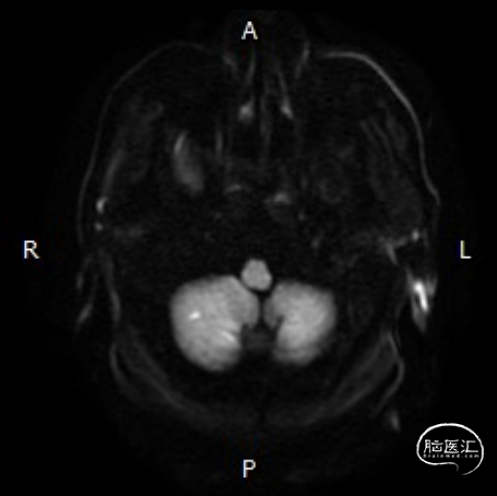

➢头颅MRI:

双侧小脑半球以及桥脑急性缺血性梗死。